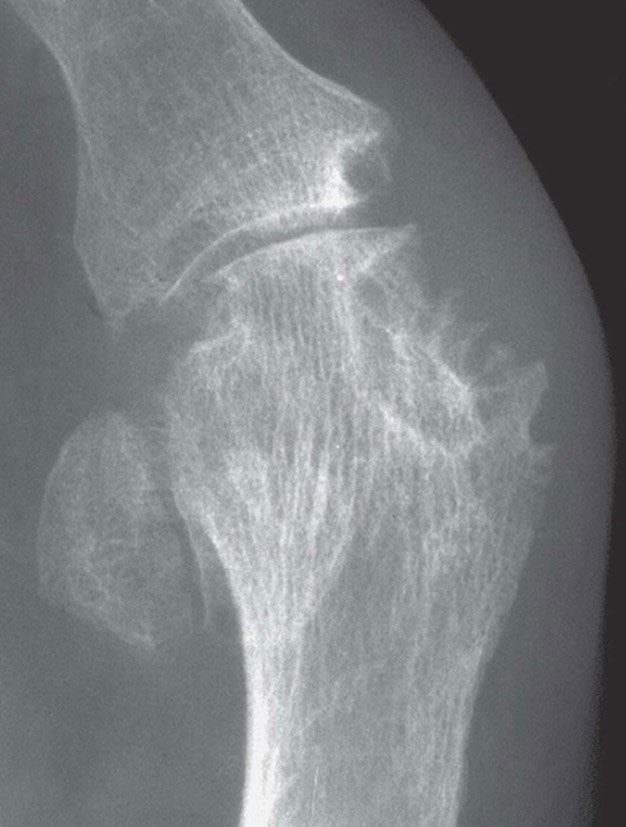

Usually, radiographs do not show characteristic features of gout until late in the disease (see figure 4, p13). However, joint ultrasound readily demonstrates characteristic features (microtophi in synovium and periarticular sites, crystal deposits in superficial articular cartilage producing a parallel double contour sign aligned with subchondral bone, and bone erosions) at first presentation in multiple peripheral sites, not just the presenting symptomatic joint.24 Dual energy computed tomography (DECT) can also identify urate crystal deposits but is less widely available than ultrasonography.